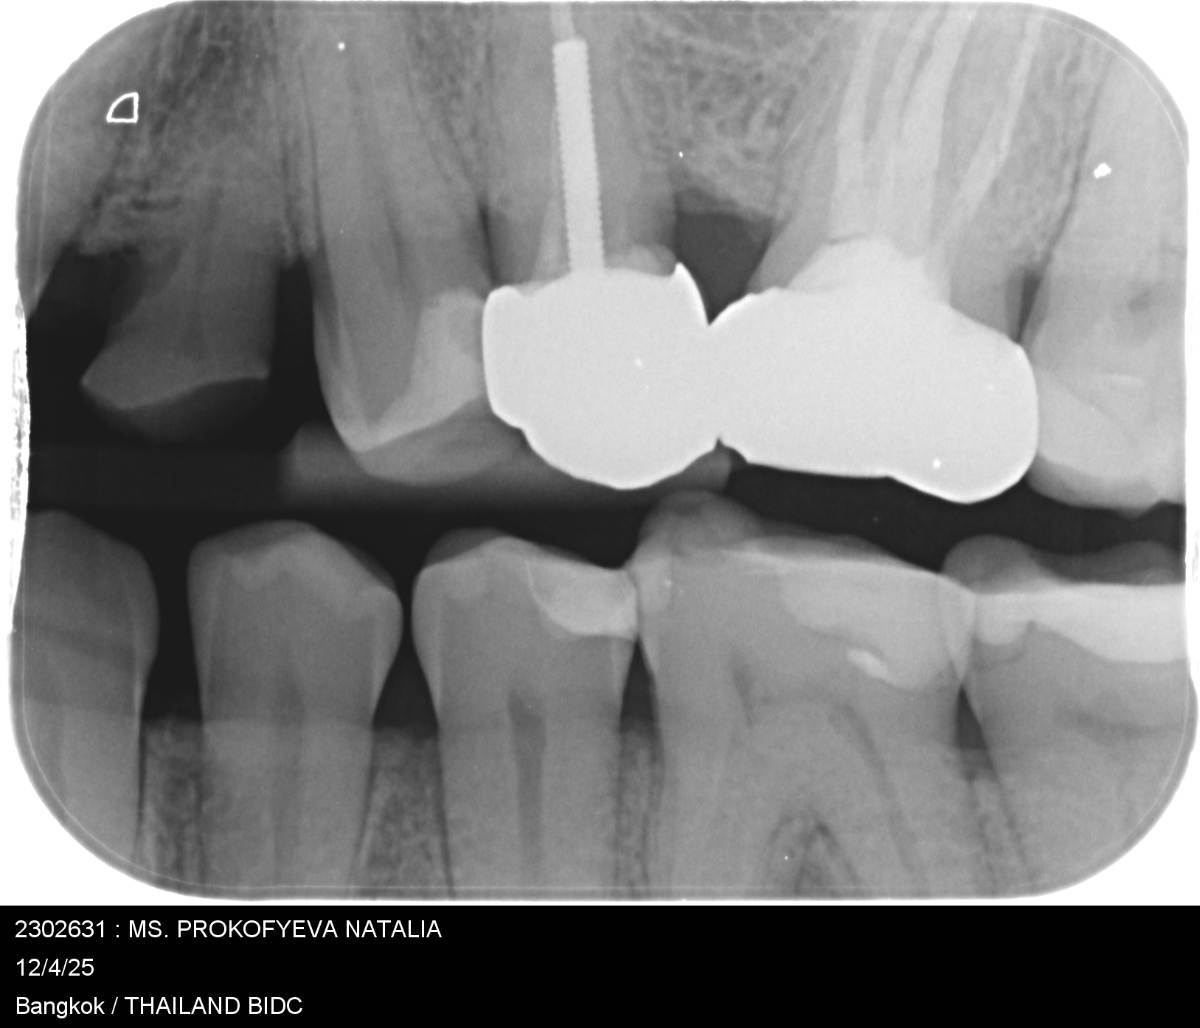

nataliapr13 Опубликовано 15 часов назад Поделиться Опубликовано 15 часов назад Здравствуйте. Где-то три года назад я ела что-то жёсткое, и зуб 26 резко заболел. Боль также возобновлялась, когда я чистила зубы ирригатором (струя вызывала резкую боль именно в этом зубе). Врач, посмотрев, предположила трещину, так как ни кариеса, ни проблем с пломбой там видно не было. Пломбу полностью удалили, но трещины не обнаружили. Через какое-то время мне удалили нервы. Зуб стал постоянно ныть. Его перелечили под микроскопом. Во время лечения врач нашла четыре канала и вскользь заметила, что есть трещина (я лечилась за границей, поэтому не совсем поняла, была ли это именно трещина). Я не стала уточнять, врач лишь спросила, хочу ли я долечивать этот зуб, и я согласилась. На перелеченный зуб поставили коронку. Всё было хорошо, но через месяц зуб снова начал ныть: то болел, то нет. Потом прошло, примерно на год наступило затишье, а затем всё повторилось. Я заметила, что боль длится максимум три дня, потом стихает. Ночью боли нет. И вот прошло три года, и зуб стал очень сильно ныть, и уже месяц это не проходит. Врач делала рентген — всё идеально, воспаления нет. Она постукивала по зубу металлическим инструментом — реакции нет. На холод тоже реакции нет, но когда я даже слегка дотрагиваюсь до него пальцем (по внутренней стенке коронки), зуб даёт реакцию. Боли как таковой нет, но есть постоянное поднывание. Есть не больно, однако через некоторое время боль усиливается на всю левую сторону челюсти, затем стихает и снова концентрируется только на этом зубе. Я чувствую его постоянно. Врач предлагает удалить зуб. Скажите, что это может быть? Похоже ли это на трещину? (на рентгене не видно что под корнями, но я делала полный рентген - там все чисто) С уважением, Наталья. Ссылка на комментарий

Doc Опубликовано 9 часов назад Поделиться Опубликовано 9 часов назад Данный снимок абсолютно неинформативен. Важно видеть верхушки корней, а их тут нет. И желательно не плоский снимок, а 3D. 1 Ссылка на комментарий